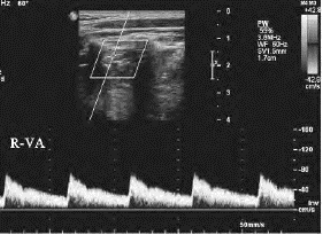

1.26.3三、正常血管

1.26.4四、动脉闭塞性疾病